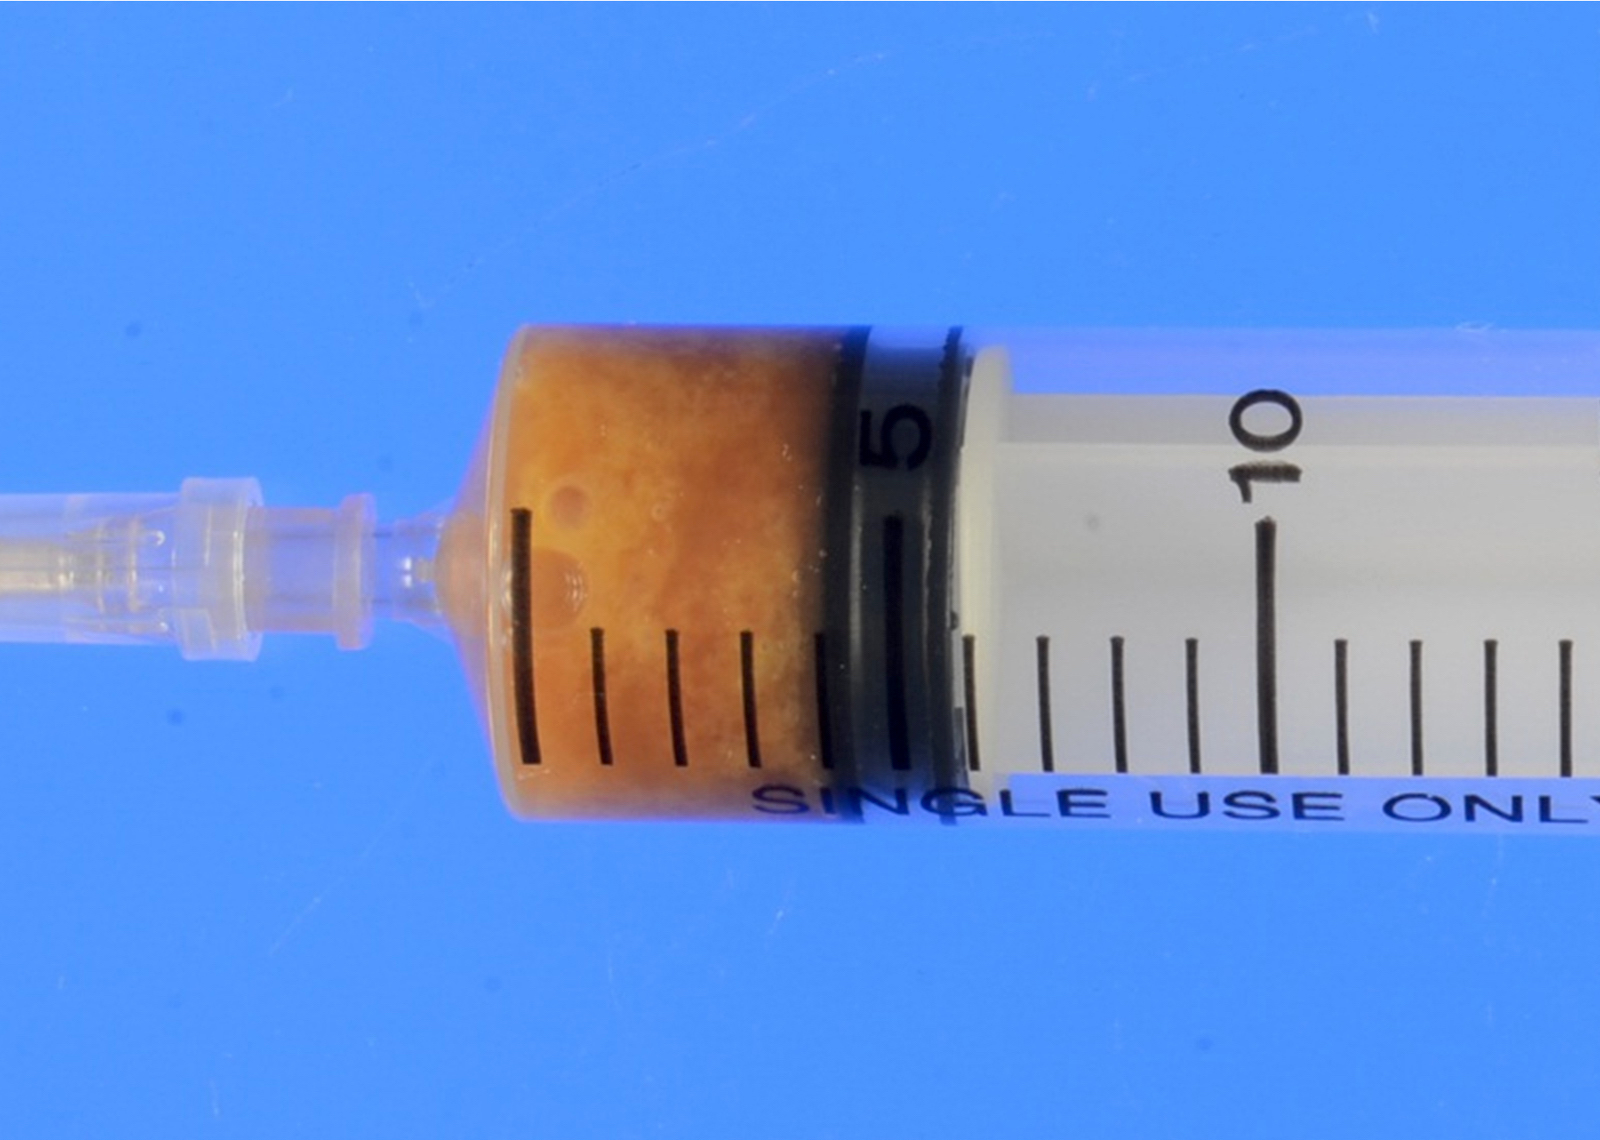

- Cystic content includes clear mucinous or viscous fluid / gel having a broad range of color (clear, yellowish tan, reddish brown and grayish white) and degree of opacity; infected cysts contain purulent exudate

Cytology description

- Preoperative FNA is moderately sensitive but with many false negatives (Diagn Cytopathol 2005;33:365)

- FNA smears are of low cellularity, with predominant inflammatory cells outnumbering epithelial cells, similar to branchial cleft cyst:

- Macrophages, either foamy or hemosiderin laden

- Mature lymphocytes and neutrophils (predominantly if the cyst is infected)

- Squamous or ciliated columnar epithelium

- Colloid is common, ranging from thick and fragmented to thin and watery

- Admixture of cholesterol crystals

- Thyroid tissue found in < 10% of aspirates, likely due to deep embedding in the cyst wall